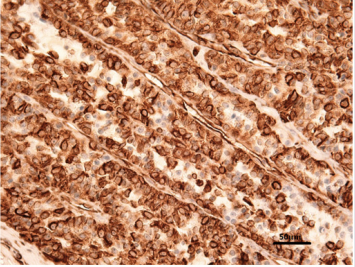

At histopathological evaluation, both round and polygonal cells, with cytoplasm rich in lipid droplets (Figure 3) giving the neoplastic tissue a foaming feature, were seen. Cellular limits were difficult to see and nuclei were ovoid in shape. Tumour cells were arranged in nests (Figure 4). Gomori reticulin staining demonstrated an abundant reticulin network around each singular tumour element (Figure 5). At immunohistochemical examinations, tumour tissue was negative for cytokeratins, strongly positive when checked with vimentin (Figure 6), positive for inhibin (Figure 7) and calretinin, whilst was negative for HBME-1.

From the histopathological exam, granulosa cell tumour, clear cell carcinoma and fibroma must be considered in differential diagnosis. The origin of the tumour was definitively demonstrated by using histochemistry and immunohistochemistry. As expected for sex cord tumours, the antibody anti-vimentin and calretinin were strongly and diffusively expressed in all tumour cells. CKAE1 and CKAE3, as well as CK7, were negative, in accordance with Akihara et al. [7]. Inhibin was slightly (as compared to vimentin expression) positive in most of the cells, described as a possible feature in dog, in histological nest type. HBME-1 immunoreaction was negative excluding the differential diagnosis of fibroma, in agreement with Banco [6]. Finally, the lack of spindle cells and the abundant reticulin highlighted by Gomori staining were consistent with a diagnosis of thecoma.